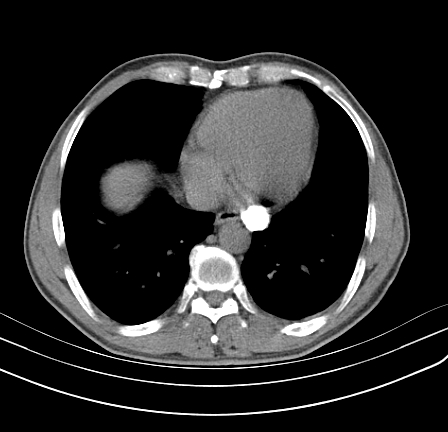

以下是引用影像孺子牛在2009-5-20 23:18:00的发言:[br]左侧后心膈角处类椭圆形钙化灶,最常见的是淋巴结钙化,但太大了不支持,其它如食管囊肿钙化、实性畸胆瘤等。何东西钙化真不好定。

以下是引用zbp537在2009-5-20 20:52:00的发言:[br]钙化灶,来源不好说。